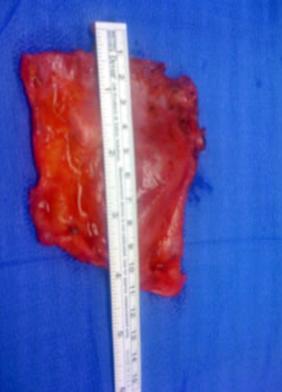

Na zdjęciach stwardniałe, obkurczone siatki usunięte w czasie ponownych operacji.